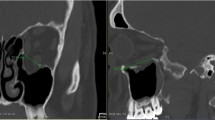

Orbital height and foil bending were measured using ProPlan CMF 3.0.1 software (DePuy Synthes, Solothrun, Switzerland, and Materialise, Leuven, Belgium). Orbital height was measured using a special algorithm that could be performed on bony reference points without fracture involvement. In the sagittal plane, approaching from the lateral side, the layer in which the superior orbital fissure was first visible was selected. In this sagittal plane, the orbital floor length—from the infraorbital rim to the posterior ledge—was measured and bisected. At the bisection point of the orbital floor, the image plane was changed to a coronal view. In the coronal image layer, the orbital height was measured in the center and 5 mm medially and laterally. Matching sequences were identified so that orbital height was measured in the same image sections for the native, fractured, and reconstructed orbits (Fig. 2).

Foil bending was calculated perpendicular to the bony supports of the foils in the coronal image section with the greatest bending of the PDS foil (Fig. 3).